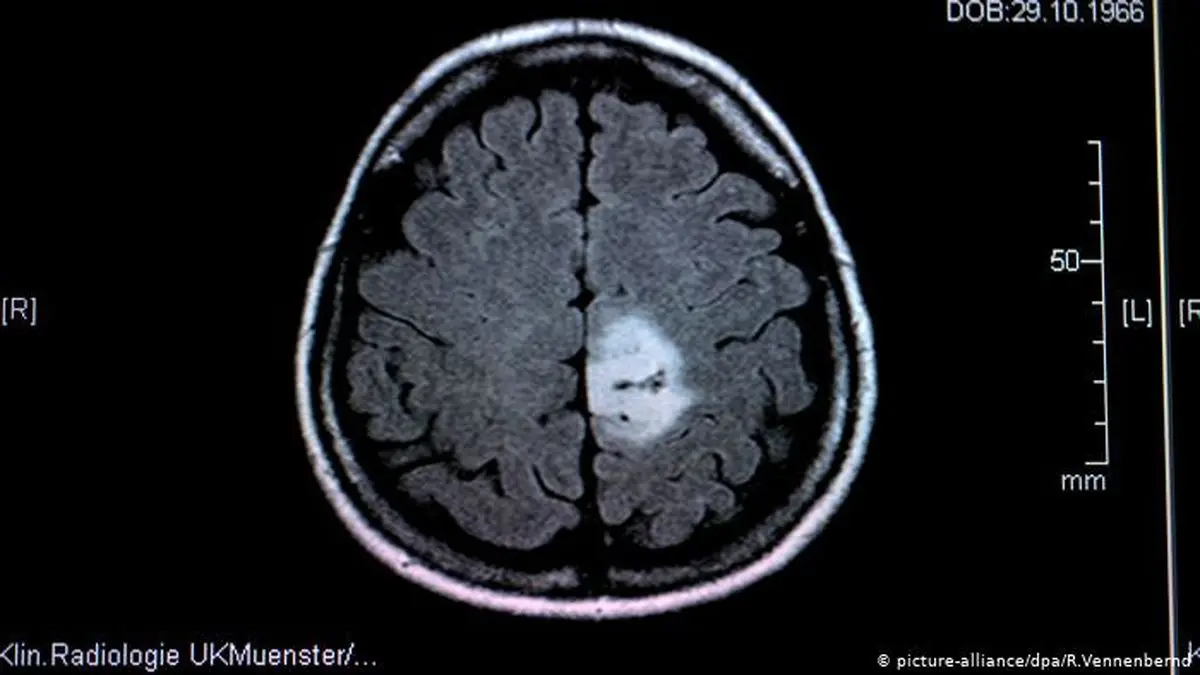

دانشمندان آلمانی: آب اکسیژنه می‌تواند از سرطان جلوگیری کند

آب اکسیژنه یا هیدروژن پراکسید معمولا به عنوان ماده‌ای سرطان‌زا شناخته می،شود، ولی تحقیقات جدید نشان می‌دهد که مقدار کم آن می‌تواند در درمان سرطان موثرواقع شود.

شرودر و تیم او موش‌هایی را آزمایش کردند که به دلیل نقص ژنتیکی قادر به تولید Nox4 نبودند. وقتی این حیوانات در یک محیط سرطان‌زا قرار گرفتند دو برابر بیشتر از موش‌های دارای آنزیم Nox4 غده‌های سرطانی تولید کردند. با توجه به تنوع غدد ایجادشده این گمانه مطرح شده است که آنزیم یادشده تاثیری اساسی در حفظ سلامت سلول‌ها دارد.

آزمایش‌های مولکولی بیشتر نشان داده‌اند که آب اکسیژنه هسته سلول‌ها را از برخی از رسیدن برخی پروتئین‌هایی واسط میان سلول‌ها که می‌توانند آنها را در ساختن دی ان ای متناسب به اشتباه بیاندازند و تکثیر سرطانی سلول‌ها را موجب شوند مصون می‌دارد.

نتیجه عام تا کنونی تحقیقات شرودر و همکارانش از آزمایش‌ها این است که حفظ تعادل در مقدار موجود آب اکسیژنه در سلول‌ها آنها را از انحطاط و تکثیر سرطانی محافظت می‌کند.